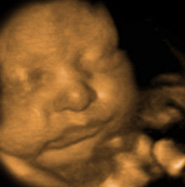

HD, 8K, and Newborn Photo Comparison

“Just wanted to shoot y’all some pics of our sweet boy and say the 8k were pretty spot on! We are very impressed with the Ultrasound and 8k .” Caitlin Anderson